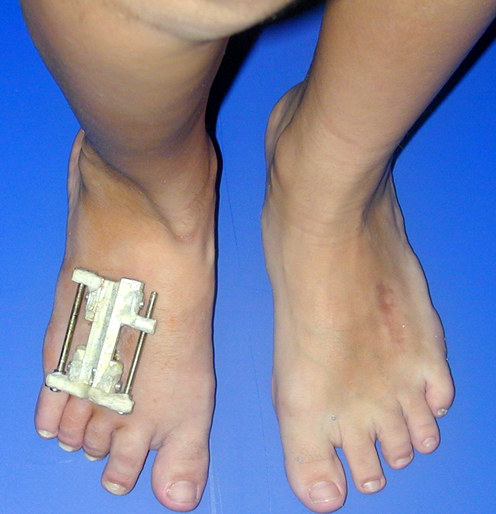

Doğuştan metakarp ve metatars kısalıklarının redavisi için pek çok teknik tanımlanmakla birlikte en çok akut uzatma sonrası kemik uçlarına greft konması ve distraksiyon osteogenezi (kallotasis) kullanılmaktadır. 1 cm.den daha fazla uzatma gereken olgularda kallotasis yöntemi önerilmektedir. Kliniğimizde de metatars ve metakarp uzatma için unilateral eksternal fiksatör ve sirküler eksternal fiksatör yardımıyla distraksiyon osteogenezi yöntemi tercih edilmektedir.

Vaka 1